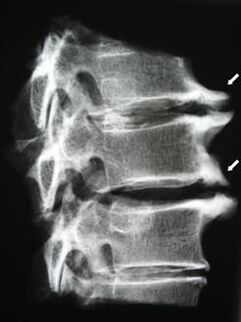

Dans les premiers stades, l'ostéochondrose est détectée par IRM. Plus tard, la pathologie peut être diagnostiquée par radiographie. Sur les radiographies de la colonne cervicale, une diminution de la distance entre les vertèbres, des modifications pathologiques des facettes articulaires et une ostéophytose deviennent perceptibles.

| Ostéochondrose cervicale | L'apparition de changements pathologiques dans un ou plusieurs segments de mouvement de la colonne vertébrale. Mobilité vertébrale altérée, développement de syndromes douloureux myofasciaux et pincement des racines vertébrales | Douleurs, paresthésies et troubles moteurs dans la région cervicale, qui se propagent à l'arrière de la tête et aux membres supérieurs. Détection de changements caractéristiques de la colonne vertébrale sur l'IRM et les radiographies (ostéophytes, diminution de la distance entre les vertèbres, signes de lésions des articulations intervertébrales) |